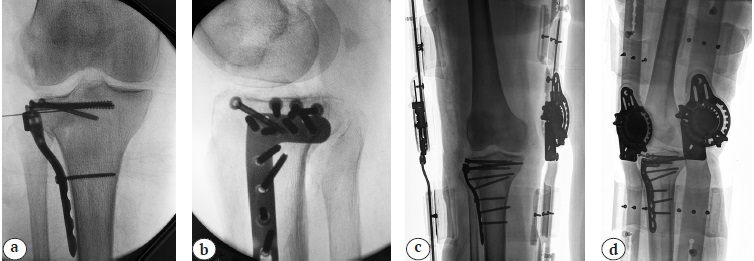

Пациентка 71 года получила травму в результате падения со стремянки. При поступлении у пациентки диагностирован многооскольчатый импрессионный перелом латерального мыщелка правой ББК 41В.3.1 по классификации АО и перелом головки малоберцовой кости (рис. 1).

Рис. 1. Рентгенограммы правого коленного сустава пациентки при поступлении в стационар: a — прямая проекция; b — боковая проекция

Fig. 1. X-rays of the right knee at the time of admission: a — AP view, b — lateral view

Операция выполнена на 12-е сут. после травмы по запланированной технике. Под спинномозговой анестезией на фоне периоперационной антибиотикопрофилактики цефуроксимом 1,0 г внутривенно, из положения на спине с согнутым коленным суставом на треугольном валике-подставке переднелатеральным доступом обнажено место перелома латерального мыщелка левой ББК. После отведения фрагмента латерального мыщелка выявлена центральная импрессия фрагментов суставной поверхности. Произведены реимпакция суставной поверхности и заполнение дефекта аллокостью. После фиксации латерального мыщелка костодержателем субхондрально установлено четыре стягивающих винта диаметром 4,0 мм. Установлена опорная мыщелковая пластина с проксимальной фиксацией пятью и дистальной фиксацией тремя винтами с угловой стабильностью диаметром 3,5 мм, после чего рана ушита послойно наглухо без дренирования (рис. 2). Время операции составило 180 мин., турникет не использовался.

Рис. 2. Рентгенограммы правого коленного сустава, отмечается удовлетворительная репозиция фрагментов плато ББК: a — интраоперационная рентгенограмма в прямой проекции; b — интраоперационная рентгенограмма в боковой проекции; c — послеоперационная рентгенограмма в прямой проекции; d — послеоперационная рентгенограмма в боковой проекции

Fig. 2. X-rays of the right knee; satisfactory reduction of the tibial plateau fragments is observed: a — intraoperative X-ray in AP view; b — intraoperative X-ray in lateral view; c — postoperative X-ray in AP view; d — postoperative X-ray in lateral view